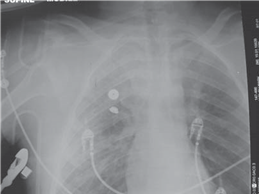

This 32-year-old pedestrian was hit by a car.

What do you see in these two radiographs?

T here is an AP view of the lower left leg showing multifragmented mid-shaft fractures of the tibia and fi bula, probably resulting from a high-energy impact. The chest radiograph suggests that there has been a signifi cant insult to the chest/lungs.

What do you understand by the term damage control orthopaedics (DCO)?

DCO is a planned and staged surgical strategy in the management of polytrauma patients to minimize the eff ects of the โ€˜second hitโ€™ on an already limited physiological reserve. The โ€˜fi rst hitโ€™ is from the injury and the bodyโ€™s response to this injury, while the โ€˜second hitโ€™ is produced by surgical intervention.

E vidence shows that, in certain patients, primary external fi xation of long bone fractures and secondary nailing improves outcome. There is a reduction in the incidence of multiple organ dysfunction syndrome (MODS) and adult respiratory distress syndrome (ARDS).

How do you decide which patients require DCO and what is the alternative?

The alternative way of managing polytrauma patients is known as early total care. This preceded the concept of DCO and involves the early treatment of all fractures. Patients who would be suitable for DCO include: those with Injury Severity Score > 20 with chest injury, those with abdominal or pelvic trauma in hypovolaemic shock (systolic blood pressure < 90 mmHg) and anyone with bilateral lung contusions.

What is the Injury Severity Score (ISS)?

T his is a scoring system based on the Abbreviated Injury Scale (AIS). Each body system is given an AIS of 1โ€“6 with 6 being the most serious. The ISS is calculated by adding the squares of the three most severely injured body systems. A patient with a score greater than 16 is defi ned as being seriously injured. In this case a patient would have greater than 10 % chance of mortality.

When do you expect to operate defi nitively on a DCO patient?

This decision will be made in conjunction with the anaesthetist and intensivist. I would usually expect this to be after at least 4 days. Parameters such as blood pressure, heart rate, arterial blood gases, and core temperature must be corrected to avoid the risk of a large second hit.

I would want to exchange from external fi xator to a nail within 10 days to avoid an increased risk of infection.